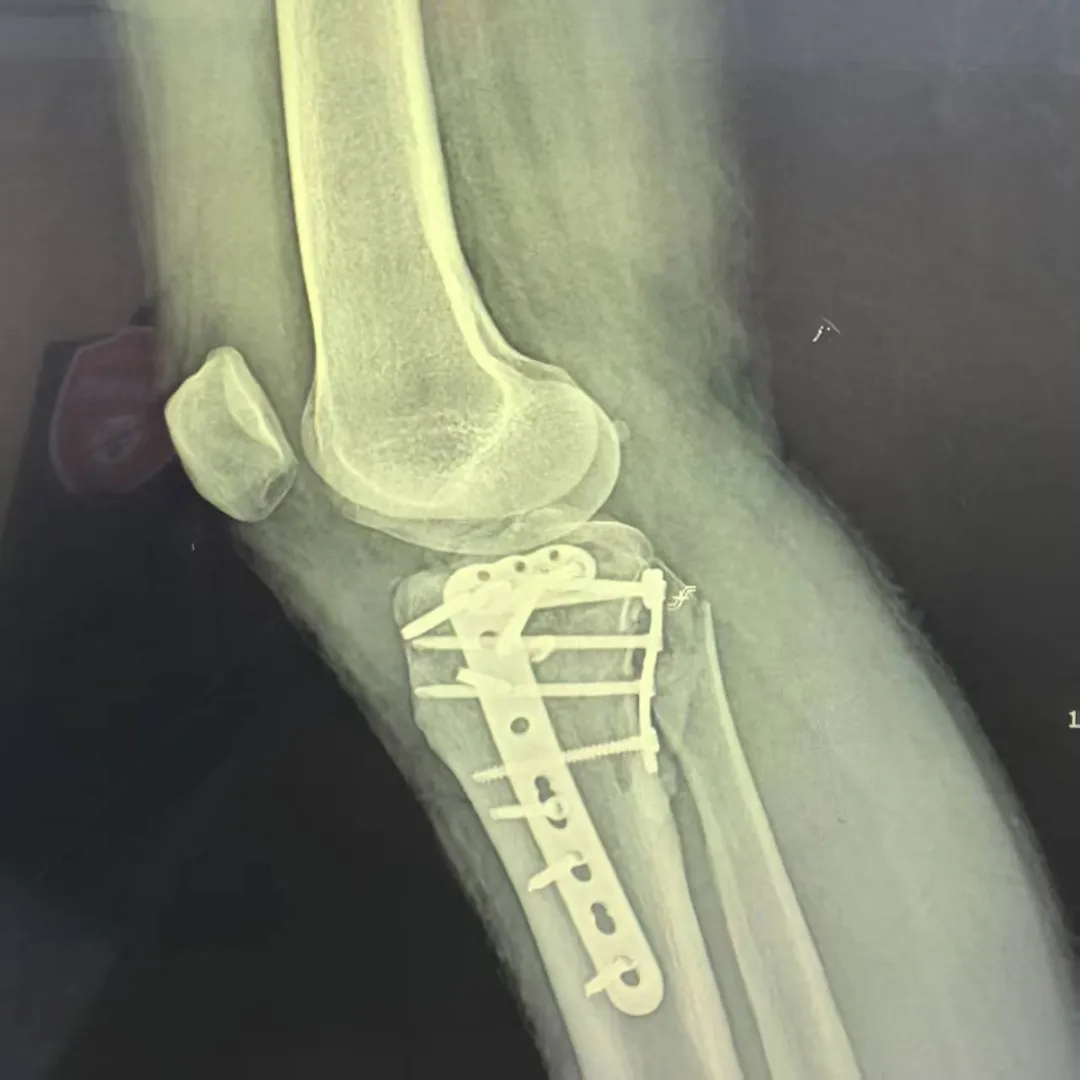

技术创新:精准手术解决方案

面对这一复杂病例,科室医疗团队组织全科进行术前讨论,结合最新版《胫骨平台骨折诊断与治疗专家共识》,经过精密规划,最终决定采用改良Frosch后外侧入路这一先进术式。

创新性采用肌间隙入路,避免肌肉损伤

在直视下完成关节面平整重建

个性化选择后外侧支撑钢板

实现骨折块的稳定固定

最大限度保护软组织血运